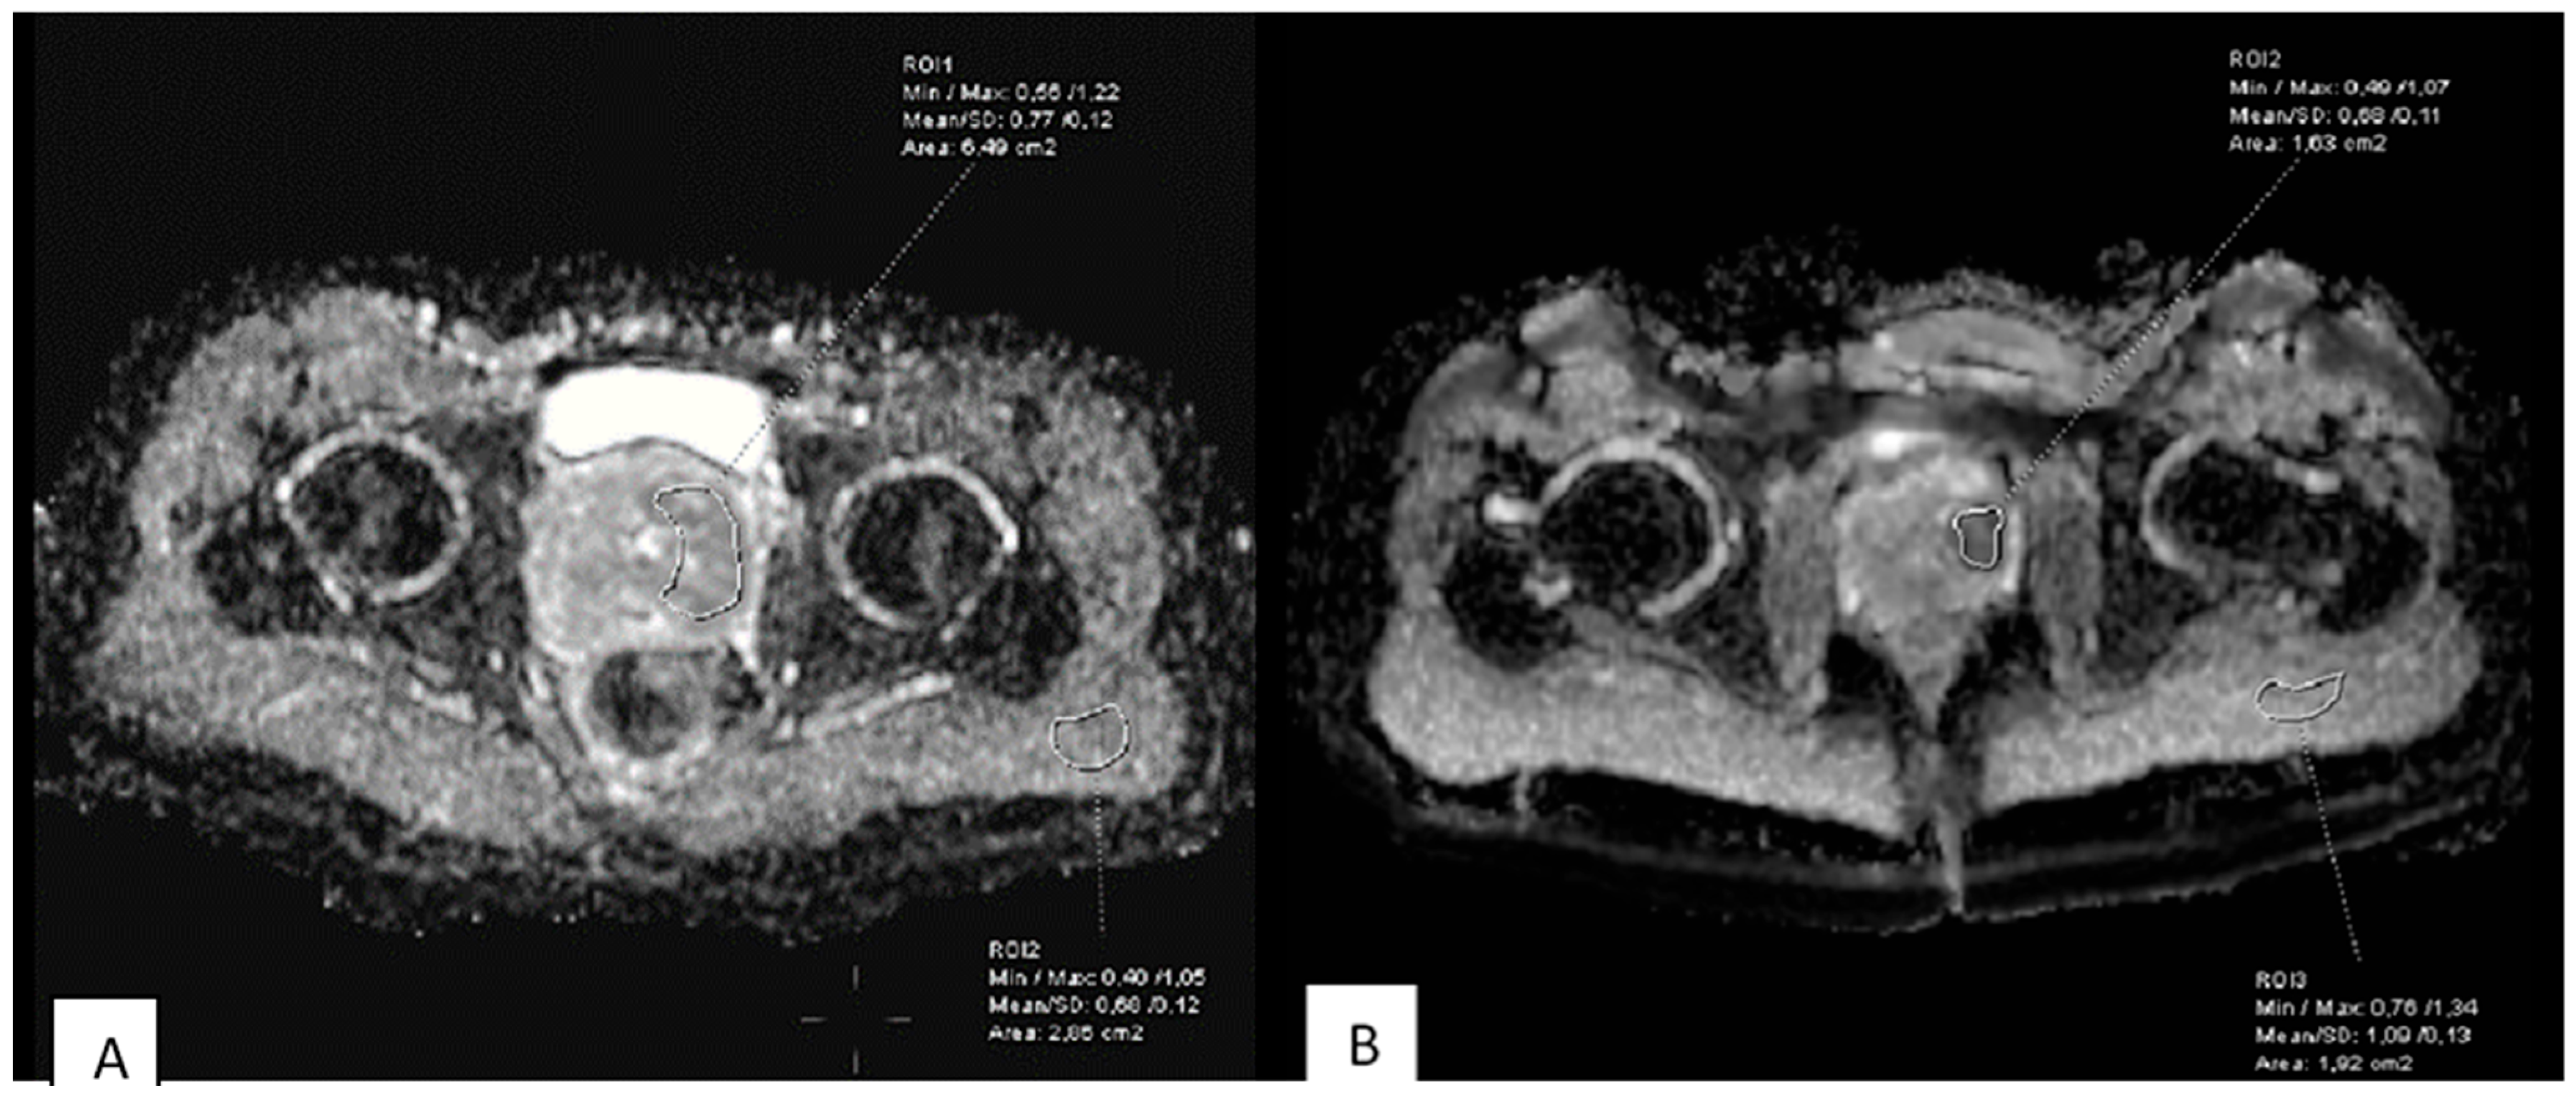

2.4. Image Analysis and ADC Measurements

3.1. Baseline Diffusion Characteristics

3.2. ADC Changes After Chemotherapy